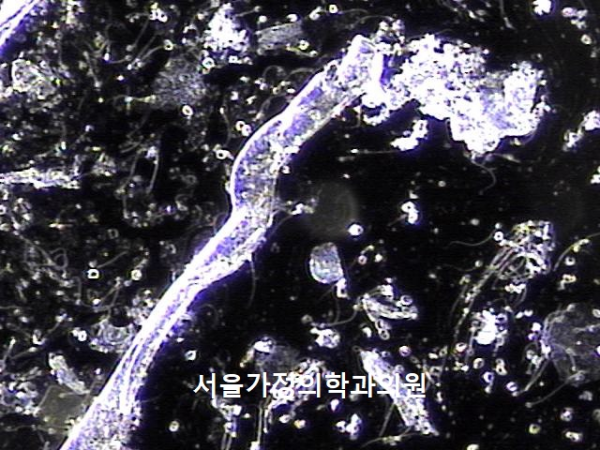

주2회 전립선의 표적 치료후 탈락된 상피세포 덩어리와 염증세포들입니다.

"Desquamated epithelial cell clusters and inflammatory cells after twice-weekly targeted prostate therapy."

주2회 전립선의 표적 치료후 탈락된 상피세포 덩어리와 염증세포 그리고 정자들이 모여 있는 정낭액의 사진입니다 .